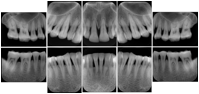

Intra-oral radiography typically involves acquisition of multiple images of various parts of the dentition. Many digital radiographic systems offer customized templates that are used for displaying the images in a study on the screen. These templates may also be referred to as mounts or view sets. The Structured Display Object represents a standard method of encoding and exchanging the layout and intended display of Structured Displays. A structured display object created in this manner could be stored with a study and exchanged with images to allow for complete reproduction of the original exam.

In most standard cases, images are oriented in structured layouts. These structured displays are useful to be shared between providers for reference purposes.

Table OO.1.1-1 shows structured display standard templates, where Viewset ID is based on the Japanese Society for Oral and Maxillofacial Radiology (JSOMR) classification provided by JIRA (Japan Medical Imaging and Radiological Systems Industries Association, www.jira-net.or.jp). Expected or typical teeth to be imaged location, region and designation codes are based on ISO 3950-2010, Dentistry - Designation system for teeth and areas of the oral cavity. For all the hanging protocols listed in OO.1.1-1, the value to use for Hanging Protocol Creator (0072,0008) is "JSOMR" and the value to use for Hanging Protocol Name (0072,0002) does not include "JSOMR" (e.g., "DL-S001A", not "JSOMR DL-S001A").